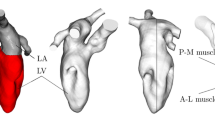

The methodology has been presented in detail in previous work,22,23 but is briefly presented here for completeness. The geometries used in the simulations included the pulmonary veins, left atrium, mitral valve, left ventricle with papillary muscles and trabeculae, aortic valve and ascending aorta, see Fig. 1. Heart valves were considered to be either opened or closed, but moved with the valve plane. Using the extracted wall motion from the CT acquisition, deformed cardiac geometries were generated every 10 ms for the entire cardiac cycle. Based on those geometries the flow field was computed using CFX 17.0 (Ansys, USA). No turbulence modelling was applied, as initial simulations showed no significant flow instabilities, and no significant turbulent kinetic energy levels were measured by 4D Flow MRI. The temporal resolution was 500 µs and spatial resolution was in the range of 9–14 million computational cells, with the smallest length scale on the order of 50 µm. Numerical schemes were second-order accurate, and blood was simulated as an incompressible fluid with density 1060 kg/m3 and viscosity 3.5e-3 Pa s. Data were saved every 10 ms. Simulation time was approximately 6–10 h per cardiac cycle using 96 CPU cores (Intel Xeon E5-2660 Sandy Bridge processors at 2.2 GHz).

Geometry of one of the patients at early systole and early diastole. During systole when the mitral valve is closed, the LA and LV are topologically separated. During diastole the mitral valve is open and the LA and LV are topologically connected. LA Left atrium, LAA left atrial appendage, RSPV/RIPV right superior and inferior pulmonary veins, LSPV/LIPV left superior and inferior pulmonary veins, LV left ventricle, AscAo ascending aorta.